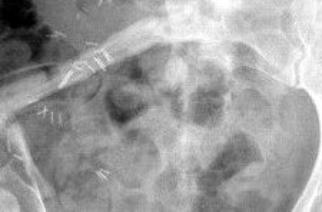

vermelden. Ich erinnert euch alle an die Bilder, die wir euch nach der Operation gezeigt haben. Hier ist es auf dem Foto noch einmal zu

sehen. Es ist ihr operativ das rechte Wadenbein aus dem Bein entfernt und als Stütze in das Becken eingesetzt worden, dort, wo vorher

die Beckenschaufel war. Das ist schon ein Meisterwerk ärztlicher Kunst gewesen. Und Gott hat Gelingen und Segen dazu gegeben. Die

Schmerzen, die Puschel in den letzten Tagen mehr hatte als sonst, rühren jetzt daher, dass der Knochen etwa an der Stelle, auf die der

Pfeil zeigt, richtiggehend durchgebrochen ist. Die Ärzte sprechen von einem Ermüdungsbruch. Der Knochen ist in der Substanz während

der Zeit der Chemo und der dadurch beabsichtigten Verhinderung der Neubildung von Zellen (Zielpunkt waren natürlich die

Krebszellen) zurückgegangen und ermüdet. Das große Problem ist, dass nun noch weniger Stabilität da ist und der Knochen erst wieder

zusammenwachsen muss. Darum werdet ihr, wenn ihr hier reinschaut, nun wieder mehr Bilder von “Puschel im Liegen” sehen. Das ist